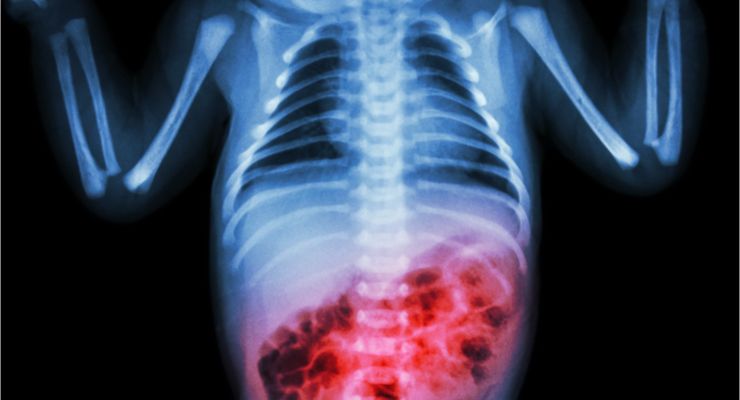

Breyts and Novac learned that Rowan had a condition that doctors called necrotizing enterocolitis (NEC). Rowan’s doctors explained that NEC is a serious disease where bacteria gets into the intestinal wall, which then leads to small holes in the intestines.

A Bacteria Invasion

Once the intestines are perforated, waste and bacteria then begin to leak into the abdomen, which causes deadly infections. The couple learned that NEC is typically seen in babies and most often occurs in infants like Rowan that are born prematurely.